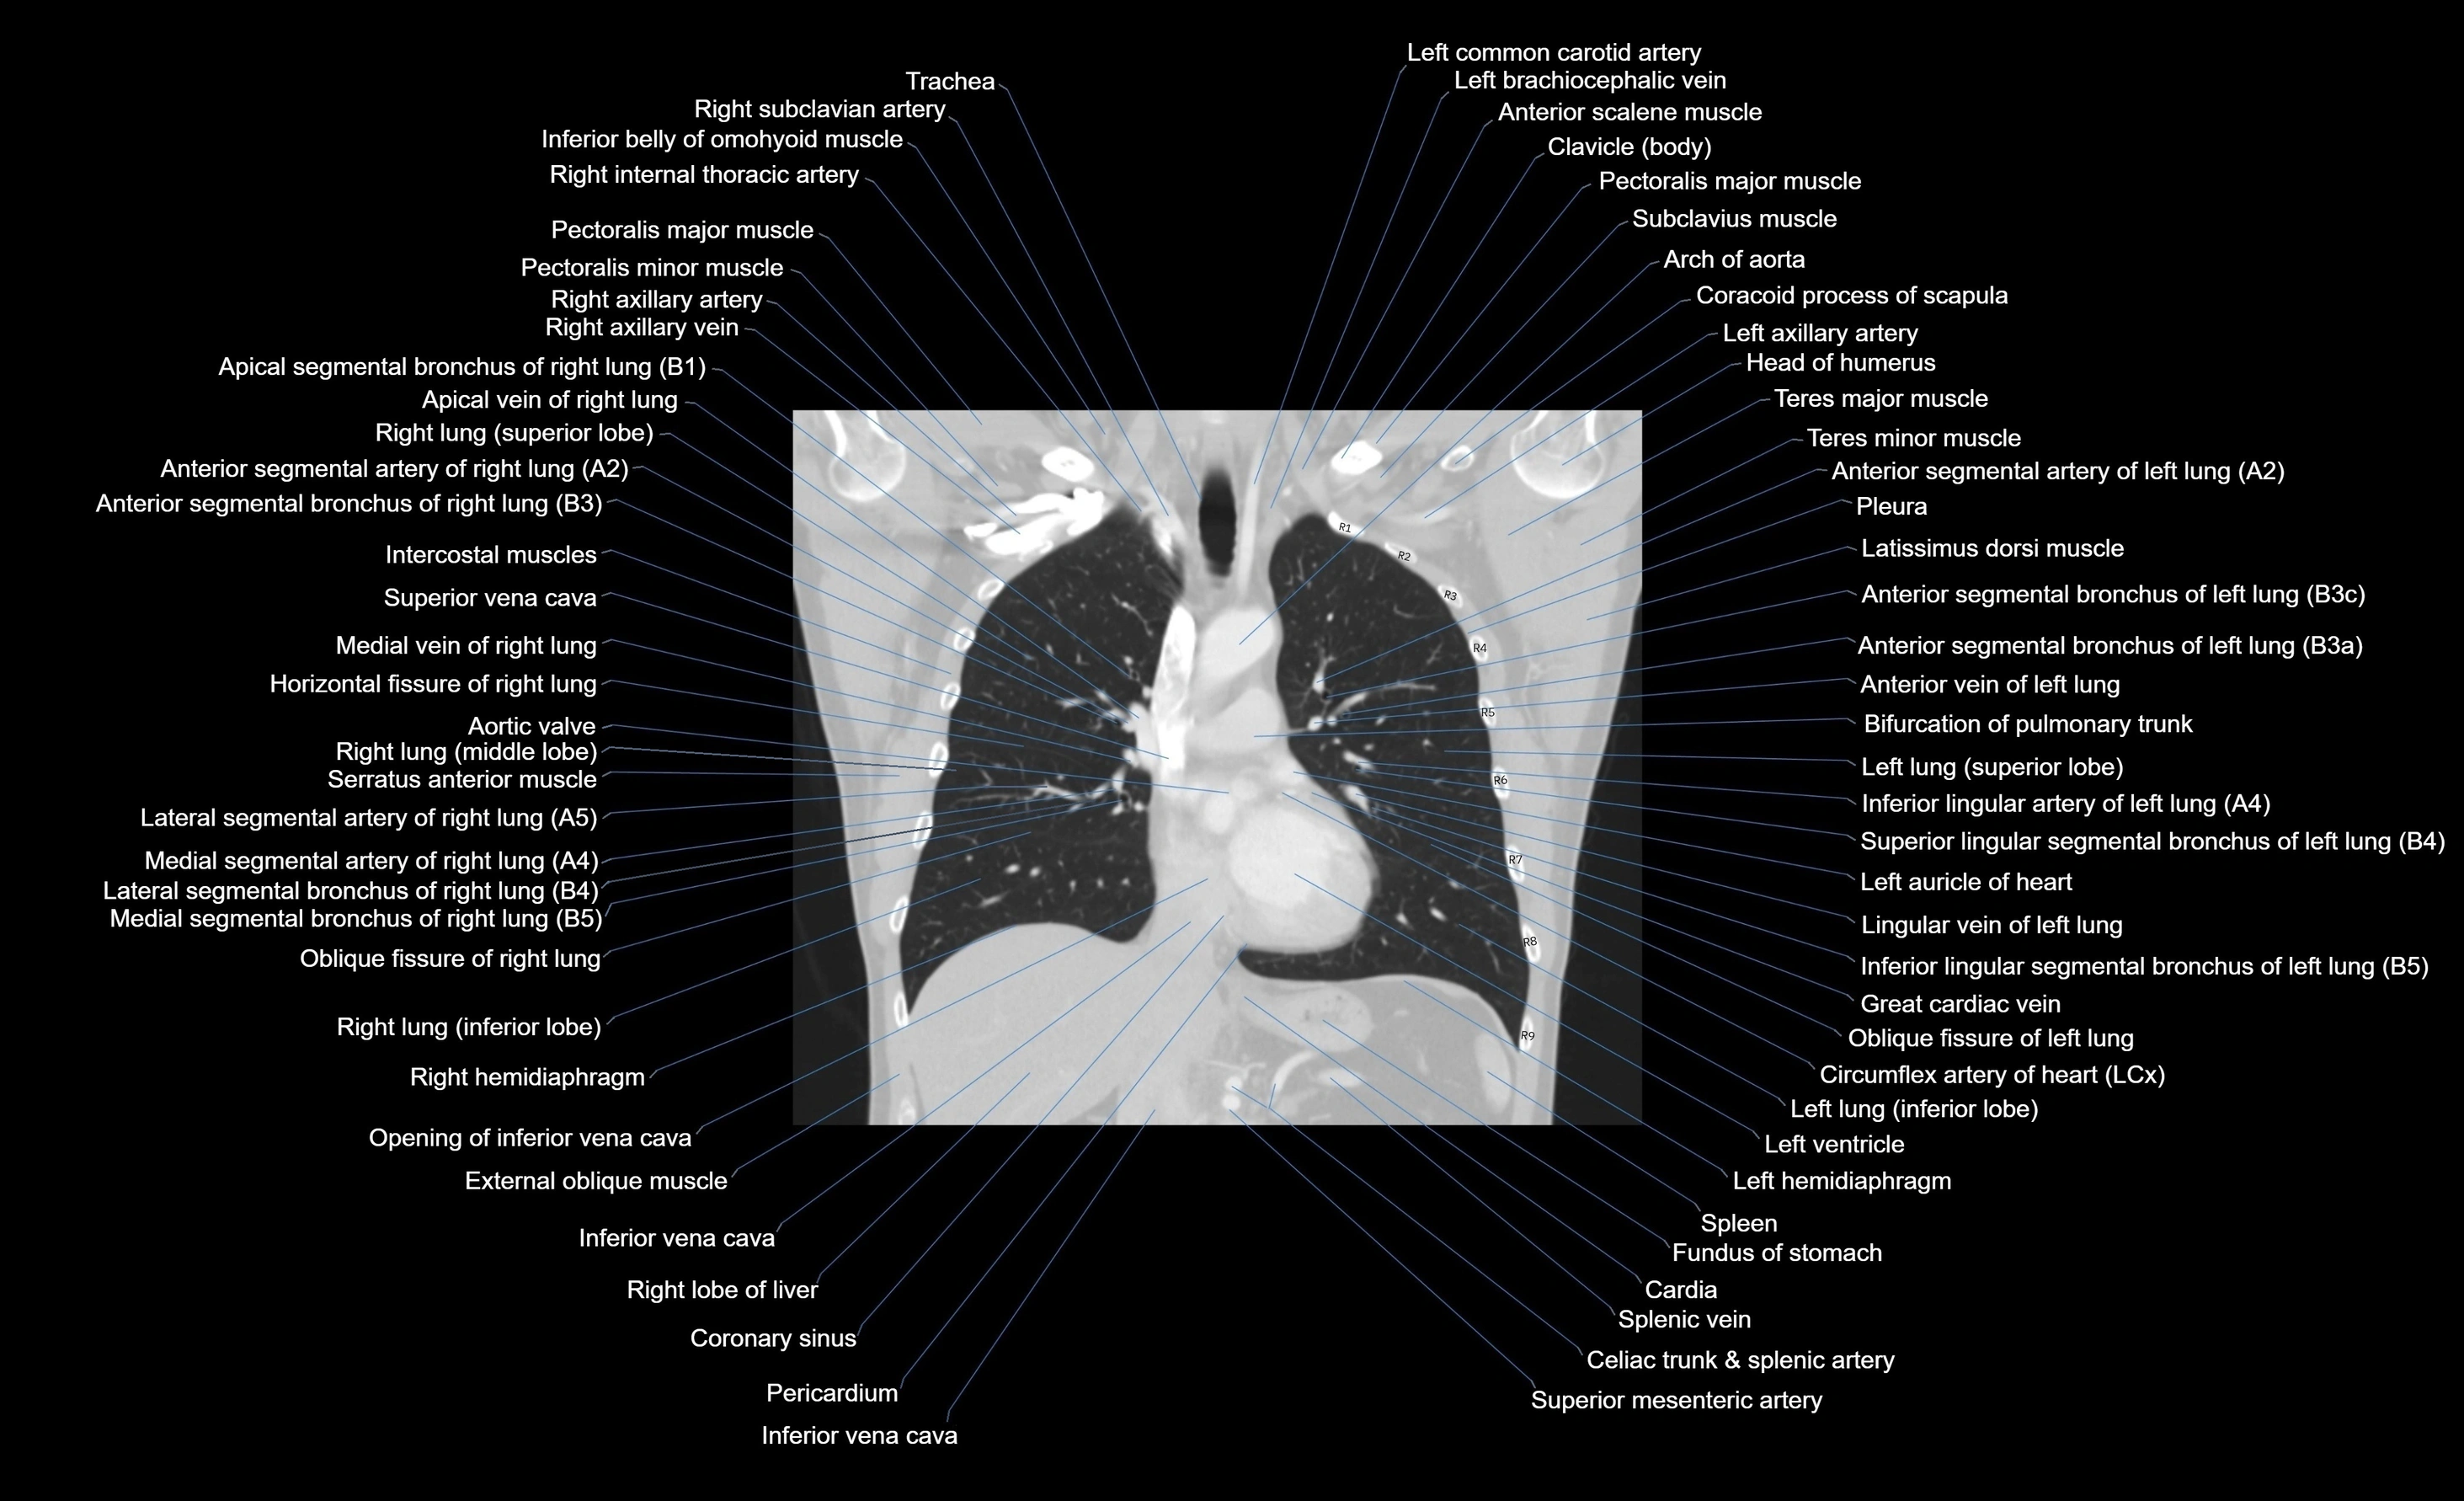

- Arch of aorta

- Ascending aorta

- Left Lung (Superior Lobe)

- Left brachiocephalic vein

- Left common carotid artery

- Left lung

- Left lung (inferior lobe)

- Pectoralis major muscle

- Pectoralis minor muscle

- Pulmonary trunk

- Spleen

- Superior vena cava